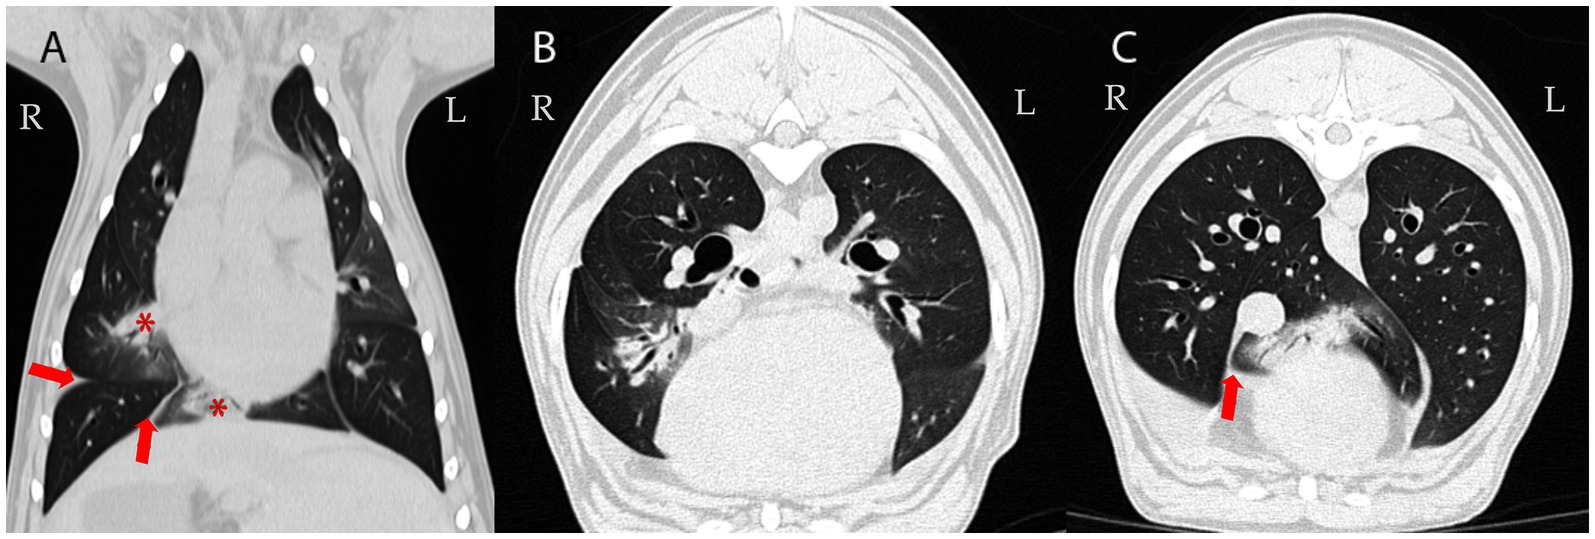

CT scans showing different views of the lungs. Panel A highlights the coronal view with red arrows and asterisks indicating specific areas. Panels B and C display axial views of the lungs, with red arrows pointing to notable regions. The left and right sides are marked as L and R respectively.

Figure 2. Follow-up CT examination 78 days later: Dorsal (A) and transverse CT images of the lung (B,C); averaged intensity projection; 0,6 mm thin section; WL -600, WW 1200. Multifocal airway-associated consolidation (demonstrated in the right middle and accessory lung lobes; asterisk in A) and pleural effusion persisted (arrows). Attenuation of non-consolidated lung parenchyma: -850 to -800 Hounsfield Units (HU) (reference range of normal lung tissue: -846 to -713 HU (34).

A 3-year-old male intact mixed-breed dog was referred to the Small Animal Internal Medicine Unit of our university for further investigation of transudative pleural effusion, chronic non-productive cough, chronic expiratory respiratory distress, lethargy, reduced appetite, and weight loss. The dog lived in an urban area with no known exposure to smoke, toxic substances, or heavy metals. The referring veterinarian had performed routine blood work, including a CBC, serum biochemistry, and C-reactive protein (CRP) testing, all of which were within normal limits. Thoracic radiographs revealed the presence of pleural effusion. Thoracic computed tomography (CT) revealed moderate pleural effusion and multiple small, round nodules in the left lung lobes, measuring 1–4 mm in diameter (Figure 1). Differential diagnoses included inflammatory lesions, granulomas, small areas of atelectasis, and neoplasia. Effusion analysis performed by the referring veterinarian, including total protein, cytology, LDH, and cell count, classified the pleural effusion as a transudate. No etiological cause for the transudate in the pleural space or persistent cough could be identified by the referring veterinarian. Prior to referral, the dog was treated with several medications, including antibiotics (amoxicillin with clavulanic acid, enrofloxacin, and doxycycline), furosemide, meloxicam, antihistamines, and a short course of dexamethasone at an anti-inflammatory dosage, without clinical improvement. However, detailed dosage regimens were not available. Upon first clinical examination, the dog demonstrated mild expiratory respiratory distress, a body condition score of 4/9, and increased lung sounds cranially on both sides, while the rest of the clinical examination was unremarkable. Upon admission, blood tests, including CBC and serum biochemistry, were repeated. The hematocrit was at the lower limit (37%; RI 37–55%), while total protein and albumin were slightly decreased (4.24 g/dL, [RI 6.00–7.50 g/dL] and 2.29 g/dL [RI 2.58–4.73 g/dL], respectively). Blood urea nitrogen was increased (48.5 mg/dL; RI 20–40 mg/dL). CRP was within normal range (0.8 mg/dL; RI < 35 mg/dL) and remained low throughout all future rechecks. After a positive fecal occult blood test, the above findings were attributed to gastrointestinal (GI) bleeding, probably due to prior treatment with meloxicam and dexamethasone. With treatment with omeprazole (1 mg/kg IV q12h), sucralfate (30 mg/kg PO q8h), and maropitant (1 mg/kg IV q24h), the GI bleeding ceased, and clinical parameters normalized within 5 days. Liver function testing (bile acids, ammonia, and coagulation panel) and serum osmolality (302 mOsm/kg; RI: 290–310 mOsm/kg) were within normal limits. Analysis of the pleural effusion confirmed a pure transudate, with a total protein of 0.5 g/dL and no inflammatory cells. Bacterial culture of the transudate was negative. Echocardiography revealed no abnormalities. Antigen enzyme-linked immunosorbent assay (ELISA) tests for Dirofilaria immitis and Angiostrongylus vasorum were negative. Fecal flotation and larval migration (Baermann–Wetzel test) for lungworms were also negative. Coagulation testing, including D-dimer and viscoelastic analysis, ruled out a thrombotic state. Serum antinuclear antibody levels were within normal limits, and serum protein electrophoresis was unremarkable. Furthermore, serologic testing for Leishmania infantum, Ehrlichia canis, and Borrelia burgdorferi yielded negative results (all below 1:20). Urinalysis was unremarkable, and the urine protein-to-creatinine ratio (UPC) was within normal range. Abdominal ultrasound showed no abnormalities except slight signs of gastroenteritis. A follow-up thoracic CT scan (Somatom X.cite VA30, Siemens Healthcare GmbH, 91,052, Germany), performed 78 days after the first one, was followed by bronchoscopy with bronchoalveolar lavage (BAL) and ultrasound-guided fine-needle aspiration (FNA) of the lung. On CT, the previously described lung nodules (round shadows) were no longer present; however, multifocal consolidation of the right lung lobes and pleural effusion were noted (Figure 2). Flexible fiberoptic bronchoscopy, along with cytologic evaluation of both the BAL fluid and the FNA from a consolidated area of the right lung, revealed predominantly alveolar macrophages with very few neutrophils and was considered unremarkable. Bacterial cultures and susceptibility testing detected very low concentrations of Pasteurella multocida, which was sensitive to amoxicillin. Polymerase chain reaction (PCR) testing for Mycobacterium spp., Toxoplasma gondii, and mycology from both the pleural effusion and pulmonary FNA material yielded negative results. After exclusion of all the above mentioned potential causes, differential diagnoses included rare causes of interstitial lung disease, such as environmental and occupational exposures (e.g., asbestosis, silicosis, and extrinsic allergic alveolitis), pulmonary alveolar proteinosis, parasitic infections (Pneumocystis carinii and Mesocestoides), A1ATD, lipid pneumonia, systemic inflammatory diseases (e.g., lupus or polyarteritis nodosa), and, finally, idiopathic interstitial pneumonia.

Computed tomography did not reveal any signs of generalized emphysema; however, acinar emphysema was confirmed histopathologically. Similar to findings described in humans (26), round- and lobular-like homogeneous increases in pulmonary parenchymal attenuation that obscured the margins of vessels, airway walls, and air bronchograms, were present on CT. Hypothetically, these changes could correspond to microparticles, such as dust or other environmental contaminants, inducing multifocal pneumonia. Unlike most human cases or other reported dogs with emphysema of different origins (27, 28), our case did not exhibit hyperlucent lung fields, diaphragmatic flattening, or even pulmonary that are responsible for decreased alveolar surface area for gas exchange and contribute to symptoms such as labored breathing, exercise intolerance, and, over time, chronic respiratory failure. Instead, multifocal consolidation (29), rather than emphysema, was primarily observed on CT scan. Moreover, the round lesions noted during the initial CT resolved over time, indicating that a major breakdown of alveolar walls leading to emphysema was not observed during CT, which had a minimal in-plane resolution of 0.4 mm. The resolution of the pulmonary nodules observed on follow-up CT suggests that these lesions were most likely transient inflammatory or infectious foci rather than permanent emphysematous changes attributable to A1ATD. This distinction is important, as emphysema caused by A1ATD is progressive and irreversible, while the disappearance of nodular opacities indicates a separate, self-limiting process. Therefore, the resolution of these lesions does not contradict the diagnosis of A1ATD but rather highlights the concurrent presence of transient pulmonary abnormalities that complicated the diagnostic evaluation. Naturally, it is not possible to differentiate interstitial pneumonia, atelectasis, or tissue breakdown from fluid-filled spaces within consolidated areas by CT. CT consistently underestimates the extent of centriacinar and panacinar emphysema, often missing most lesions less than 0.03–0.04 cm in diameter (30), and is considered insensitive in detecting the earliest or smaller emphysematous lesions in humans (30). This limitation probably applies even more to smaller dogs. However, high-resolution CT was not performed (31). Despite CT’s limited spatial and contrast resolution, histopathology provided significantly higher sensitivity for detecting or confirming acinar emphysema. However, CT showed that the lung was not overinflated.